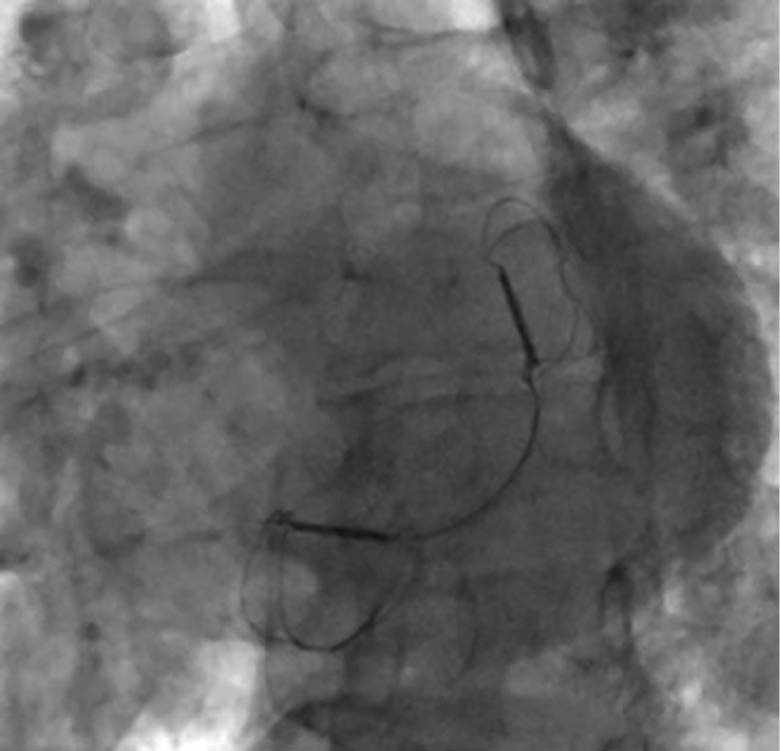

Abbildung 3c: Endergebnis des CARILLON®-Systems

unter der Fluoroskopie

Die Implantation eines 60-mm-Carillon®-Systems erfolgte unter fluoroskopischer und TEE-gestützter Kontrolle nach vorheriger intraprozeduraler Größenauswahl und Anpassung in Analgo-

sedierung. Die Implantation verlief komplikationslos. Eine angiographische Kontrolle schloss eine relevante Kompression des RCX und der RCA aus. Die Interventionsdauer betrug 45 Minuten, die Durchleuchtungszeit 11 Minuten.